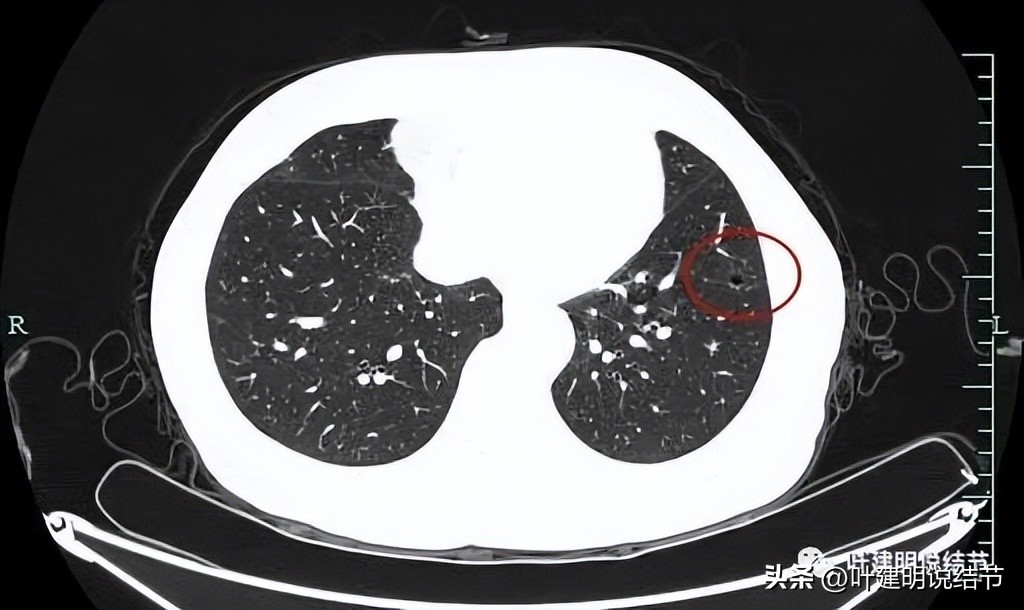

再看左下叶的主病灶,此层见其是磨玻璃密度,轮廓较清,内部密度欠均匀。

有明显血管征,血管进入后有分支发出,病灶表面显得有毛刺样。

病灶中间有空腔。

囊壁较薄,但不均匀,有的地方还是显略厚了点的。